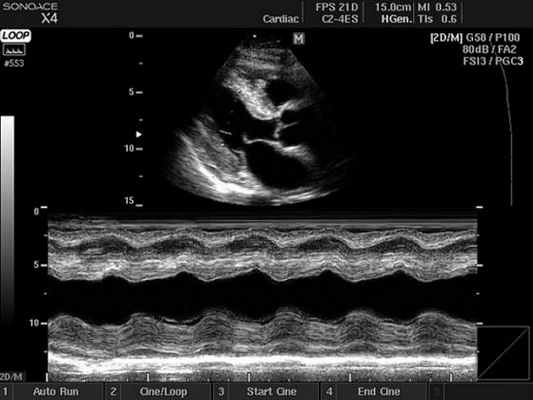

2. М-режим - графическое изображение движения стенок сердца и створок клапанов во времени. М-режим позволил впервые в реальном времени оценить размеры сердца и систолическую функцию желудочков. В настоящее время применяется как вспомогательный режим при проведении эхокардиографического исследования преимущественно для измерений. В том случае, когда в парастернальной позиции курсор М-режима располагается строго перпендикулярно изображению сердца, измерения могут быть проведены с большой точностью. Если изображение сердца и курсор расположены под углом, все размеры камер сердца будут значительно завышены и могут быть неправильно истолкованы. Эта ошибка встречается у специалистов с небольшим стажем работы. Поэтому следует проводить измерения в B- режиме в конце диастолы в том случае, если М-режим не может быть применен. В настоящее время ряд фирм предложили использовать анатомический М- режим, позволяющий изменить угол курсора.

На графике М-разверстки по вертикали откладывается расстояние, по горизонтали - время. В зависимости от положения курсора на экране, можно получить график колебания серии точек, расположенных вдоль курсора, вытянутый во времени, т.е. проследить за их колебанием в систолу и в диастолу.